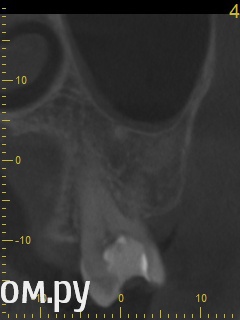

Анатолий М Опубликовано 21 апреля, 2014 Поделиться Опубликовано 21 апреля, 2014 Добрый день. Помогите пожалуйста.17 зуб (верхняя семерка с права). Пол года назад был депульпирован. Все это время присутствуют боли под этим зубом по симптомам очень похожие на кисту (распирание, боль ноющая не сильная, то появляется то сама собой изчезает. при перкуссии 17 зуб слегка болезненный). 2 месяца наза решили зуб перелечить. На ОПТГ ситуация до перелечивания. По снимку видно что первоначальное лечение было проведено плохо. Корни были плохо пройдены и плохо заполены цементом.Месяц хождения с гидроокисью кальция на воде никакого эфекта не дали. Врачи считают что под зубом есть киста. И предлагают удалить зуб. Так как перелечивание не помогло.Прилагаю снимок КЛКТ после лечения. Зуб все еще под временной пломбой. Из трех врачей лишь один разгледел на КЛКТ кисту под 17 зубом. Два других ни на КЛКТ ни на прицельных никакой кисты не видят. Направили к неврологу. Думают что киста если она и есть (в чем они не уверены) не дает имеющихся симптомов.Пожалуйста посмотрите на КЛКТ. Есть ли там киста или нет? И могут ли боли быть от нее?Заранее спасибо. Ссылка на комментарий

Анатолий М Опубликовано 21 апреля, 2014 Автор Поделиться Опубликовано 21 апреля, 2014 Снимок во время лечения делали? Коффердам и оптика использовались? На кт в тех срезах что Вы выложили кисты не вижу Снимки во время лечения делали три раза прицельные с иголками в каналах. Но они остались у врача. У меня их нет. Но она по ним кисты не видела. Коффердам использовали только при первом посещении когда вскрывали старую пломбу и прорабатывали каналы. При последующих посещениях при смене лекарст его не использовали так как кольцо на зубе плохо держалось и постоянно слетало. Плюс травмировало десну.Микроскоп использовали все три раза. По словам врача (врач высшей категории эндодонтист зав отделением):При вскрытии старой пломбы каналы практически не заполены цементирующим составом. Иструмент при вскрытии пломбы в каналы проваливался. Хотя стояла постоянна пломба. Из трех каналов лишь один был проработан до верхушки корня. Два других либо до половины либо на треть. Врачь полностью прошла все каналы и даже залезла за апекс. туда при первом пломбировании врач даже не пыталась лезть. При третьем посещении врач констатировала что каналы чистые. Никаких признаков инфекции нет. И белезненная перкуссия от чего то другого. Специально проводила ревизию каналов при втором и третьем посещении без анастезии что бы понять где болит. Но так и не поняла. Повела на консультацию к профессору в их стоматологи. Посмотрев контрольную КТ он сказал что там киста и надо удалять зуб! Похоже что мой врач с ним не очень согласна, хотя и спорить не стала поэтому отправила меня на консультацию к неврологу. Ниже срезы конрольного КТ после месяца лечения гидрооксидом кальция на воде. Срезы по дуге. Сделал как смог. Шаг срезов как я понимаю 1мм. Линия по перек дуги снимок номер 1 (см нумерацию в конце названия файла) Ссылка на комментарий